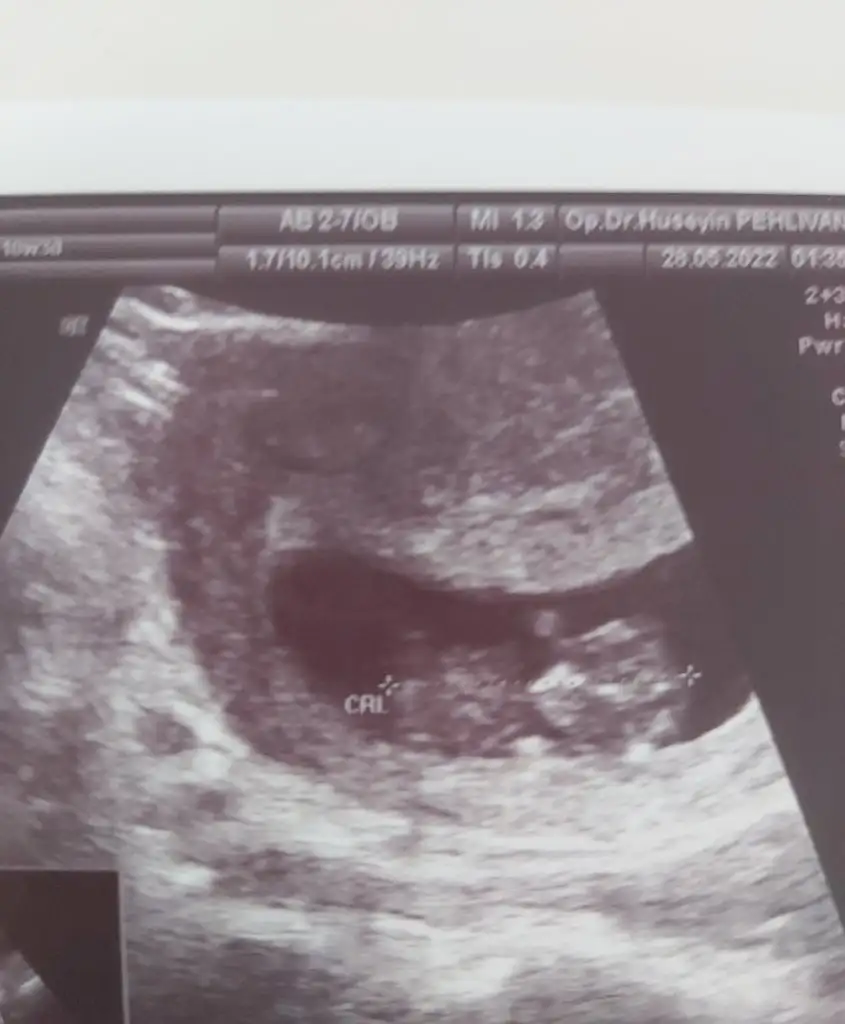

9+5 karından çekildi tahminde bulunur musunuz

• Screenshot_20220528-154026_WhatsApp.webp

Screenshot_20220528-154026_WhatsApp.webp

8,4 KB · Görüntüleme: 74

• 20220528_132759.webp

20220528_132759.webp

21,2 KB · Görüntüleme: 63

Neye göre yorumluyorsunuz 9 lu haftalarda çünkü ramzi geçersiz oluyor bu haftada

iki görüntünüzde çok farklı birinde U şeklinde keseniz paşa gibi ikinci fotonuzda dümdüz paralel oda kız gibi o yüzden 7-8 ve 11-12-13 haftalarda en doğru tahminler yapılıyor genelde

Ha ben ilk görüntüyü videodan ekran resmi olarak çektim doktorun esas verdiği ikinci resim